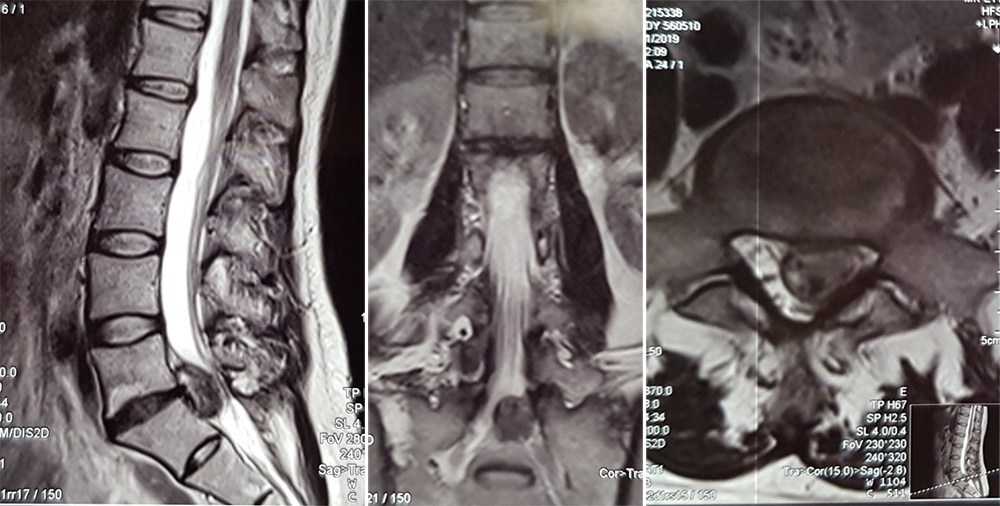

КТ-протрузии дисков: Визуализация и классификация